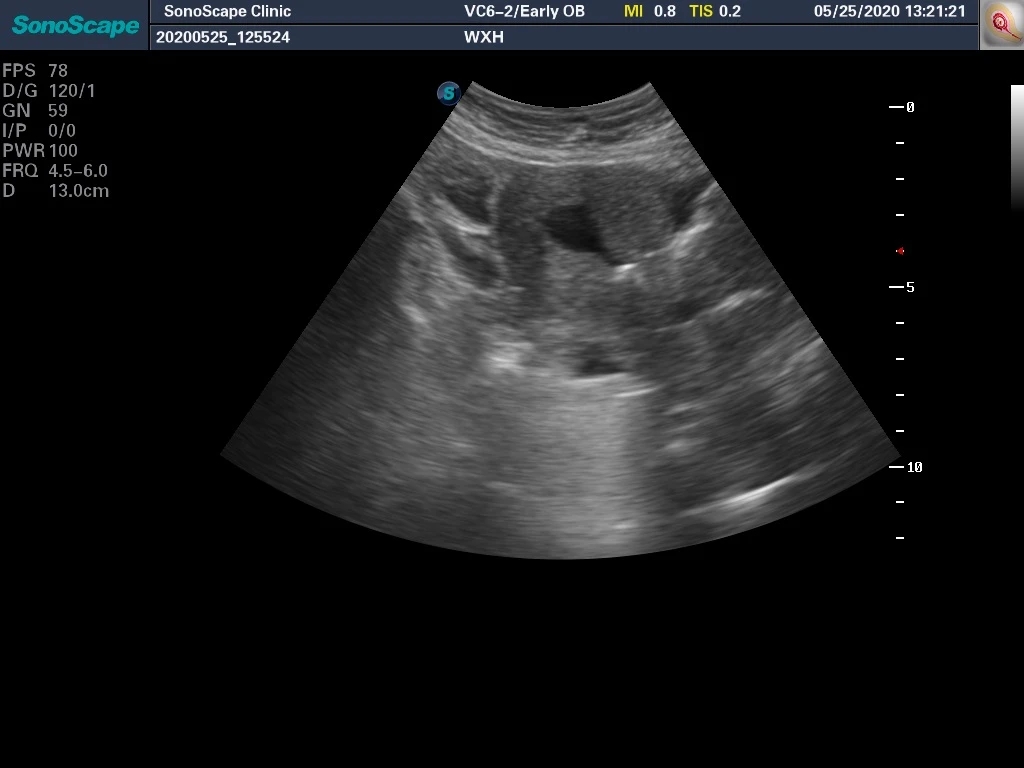

返回彩超,看看术后的情况。下图展示的是宫腔恢复后的容积,显然远远大于手术前两个小空间的面积。

这台彩超还允许我们在手术中直接进行3D重建成像。

上图白线所标记部位就是恢复后的整体子宫腔,与正常的宫腔相比已经无明显差异。

通过2D手术引导及床边3D彩超重建,我们可以大大提高手术的效率及安全性,在过去,类似的手术可能就要借助腹腔镜引导、临时球囊扩张后二期分粘等其他手段,而使用彩超引导技术,既可以完成手术中引导,避免进入“假腔”或者“子宫穿孔”,还可以手术结束立即评估,如果觉得手术没到位可以及时补救,大大减少各种手术并发症的可能性。